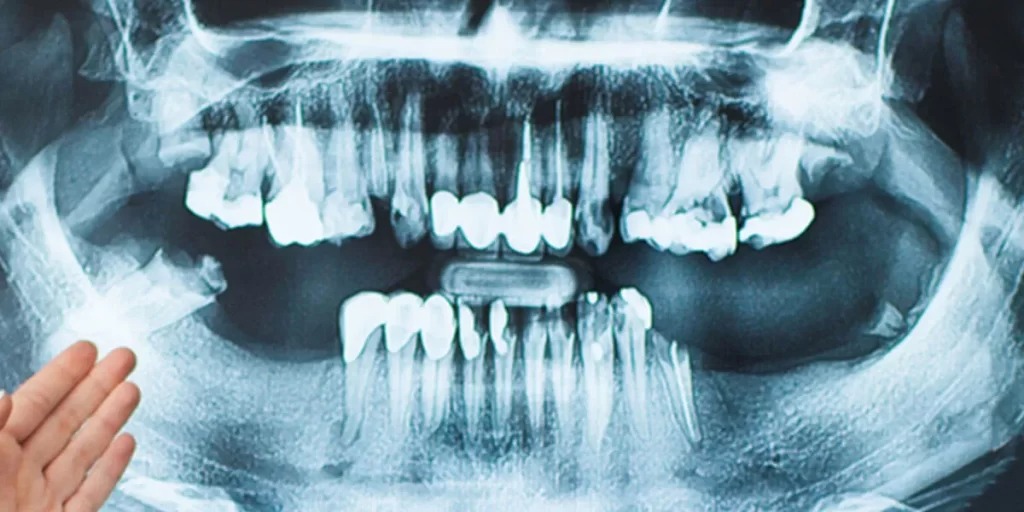

- Chụp X-quang Panorama – Cho hình ảnh tổng quan toàn bộ hai hàm, giúp đánh giá sơ bộ mức độ tiêu xương.

- Chụp CT Cone Beam 3D – Đây là “vũ khí” chính xác nhất. Hình ảnh 3D chi tiết cho phép bác sĩ đo chính xác chiều cao, chiều rộng, mật độ xương còn lại.